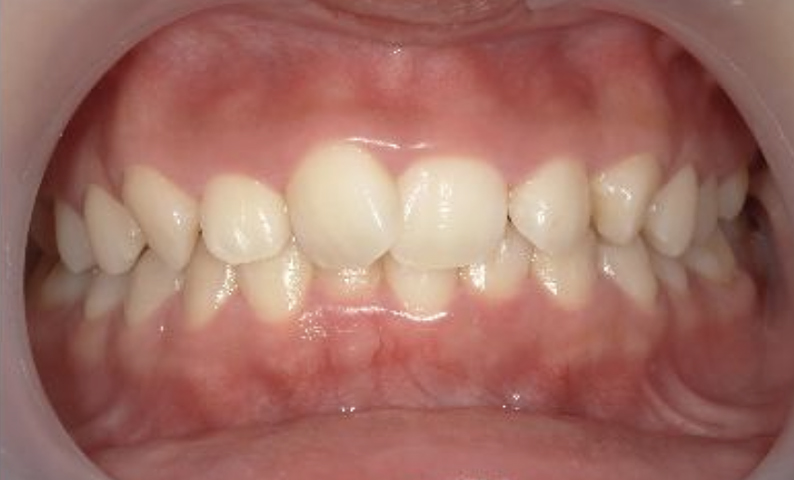

症例_004 上下顎の部分矯正

治療期間:8ヶ月金額:54万円+税女性前歯のガタガタ捻転歯